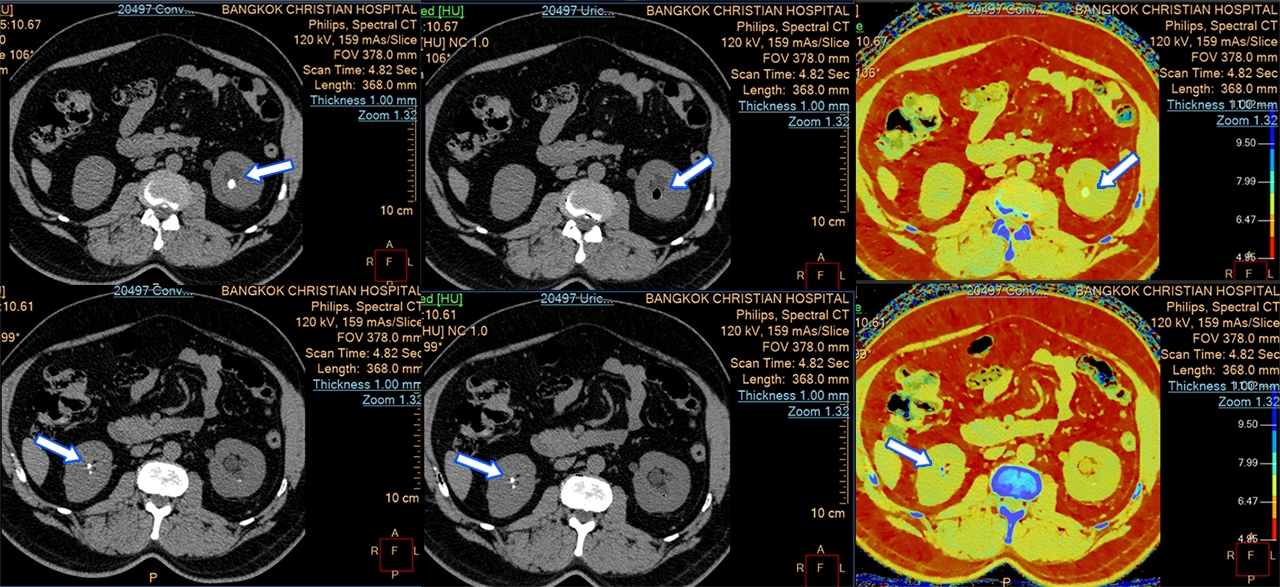

ตรวจนิ่วและเกาต์ได้ละเอียดยิ่งขึ้น ด้วยความสามารถในการแยกแยะองค์ประกอบทางเคมีในร่างกาย เช่น กรดยูริก ทำให้แพทย์สามารถระบุชนิดของนิ่วในร่างกายผู้ป่วยได้อย่างแม่นยำ นำไปสู่วิธีการรักษาที่มีประสิทธิภาพสูงสุด สำหรับผู้ป่วยเกาต์ เครื่องนี้ไม่เพียงแค่ช่วยในการวินิจฉัยโรค แต่ยังสามารถวัดปริมาตรรอยโรคในข้อและสร้างเป็นภาพ 3D ให้แพทย์ตรวจสอบได้ในคราวเดียว

(แถวซ้าย: ภาพ CT ทั่วไป / แถวกลางและขวา: ภาพ Spectral CT)